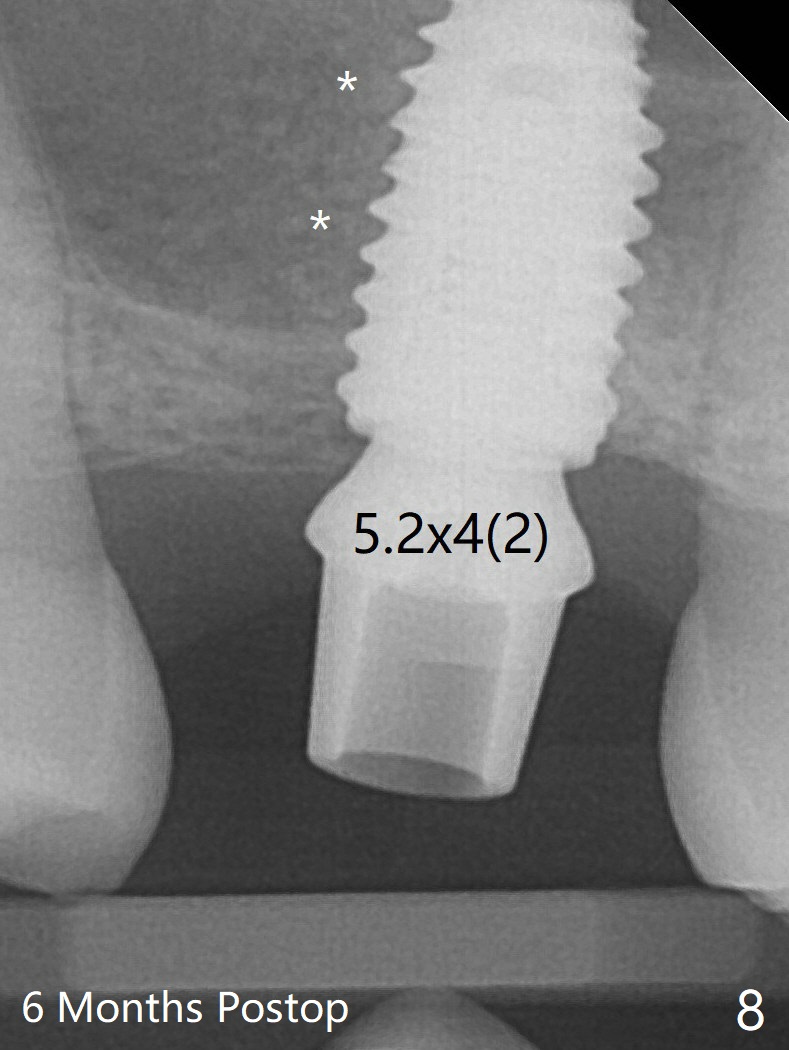

A 4.5x10 mm dummy implant is placed with high torque after 4x7.3 mm drill with 3 mm stopper so that 4.5x7.3 mm drill with 1 mm stopper is used before placement of a 5x8.5 mm final implant with ~ 35 Ncm (Fig.6-7). There is no pain when a 5.2x4(2) mm cemented abutment is torqued at 30-35 Ncm before impression (Fig.8). *: bone graft in the sinus. When the permanent crown is delivered, the patient feels light pain when she bites hard. The discomfort persists 4 months post cementation (Fig.9). The crown/abutment is replaced with a healing abutment (Fig.10).